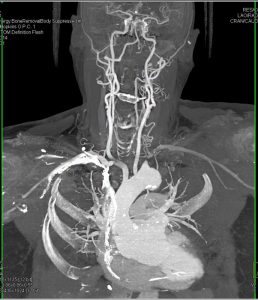

КТ-ангиография сосудов головы и шеи - диагностический метод, позволяющий послойно просканировать кровеносное русло и преобразовать снимки в детализированную трехмерную картинку. На основании полученных данных врач-рентгенолог делает заключение о наличии либо отсутствии нарушений.

Компьютерная томография сосудов головы и шеи - объемная реконструкция

3D-КТ-ангиография сосудов головного мозга

Фото КТ сосудов головы и шеи

На снимках ангиографии шейных и головных сосудов визуализируются:

крупные артерии со своими ветвями:

передняя, средняя, задняя мозговые артерии и сосуды, участвующие в образовании Виллизиева круга вместе с ними;

сонные (общая, наружная, внутренняя);

позвоночные и основная артерия;

синусы твердой мозговой оболочки;

КТ шейных сосудов (объемная реконструкция). На изображении можно увидеть пример кинкинга (патологической извитости) и аневризм (колбовидных расширений) экстракраниальных сегментов внутренних сонных артерий

Также по фото компьютерной ангиографии выявляют коллатерали - обходные кровеносные пути, активизирующиеся при проблемах с проходимостью магистральных артерий (окклюзии, стенозе, повреждениях и т.д.).

Компьютерные томограммы сосудов головного мозга и шеи